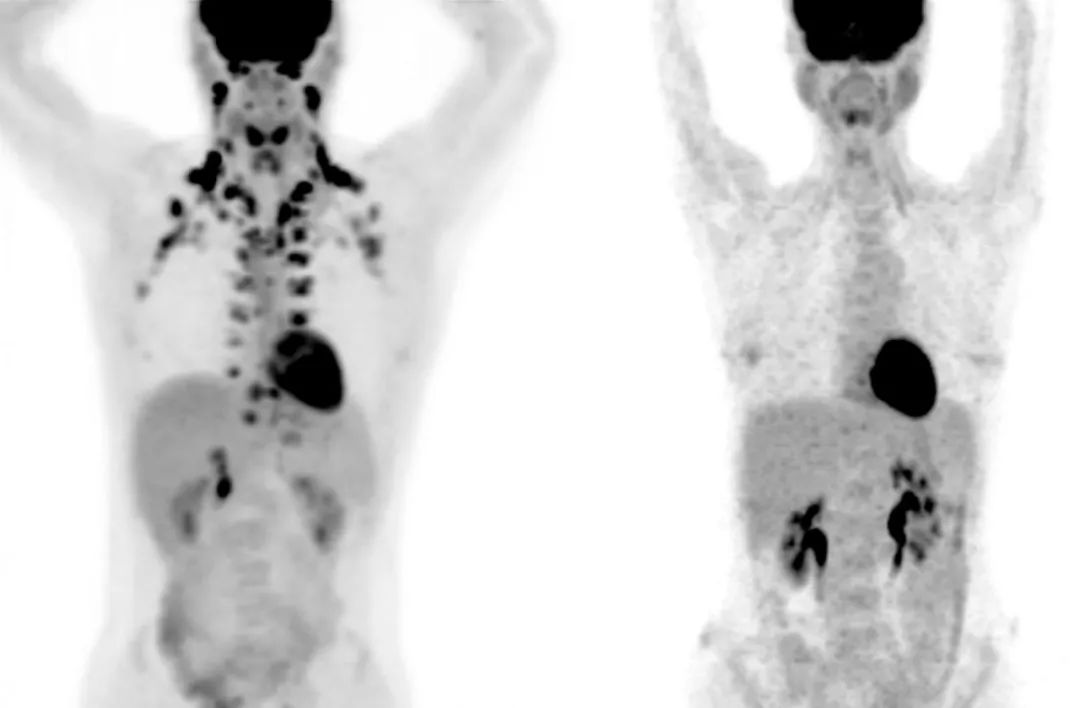

左图是颈部和锁骨部位有棕色脂肪的人,右图则没有(图片来源:MSKCC  Andreas G。 Wibmer & Heiko Schöder)左图是颈部和锁骨部位有棕色脂肪的人,右图则没有(图片来源:MSKCC  Andreas G。 Wibmer & Heiko Schöder)

但在之前,应该没有人能这么明确地得出上面的推断,毕竟成人身体存在BAT也是最近十几年才被研究证实的,2009年《新英格兰医学杂志》的研究确认,BAT是糖类和脂肪酸的代谢中心区域,且大多位于颈部和锁骨区域。在更早些时候,科学界认为BAT只存在于一些动物和人类婴儿体内,主要用来弥补年幼不发达的颤抖产热行为。而现在,BAT已经被定义成了一个重要的产热器官。

Beche意识到,这里或许是一个真正有大量BAT样本数据的资源库。在与对方沟通合作过后,Beche拿到了病人的PET扫描数据,一共有超过5.2万名病人的13万张扫描图。根据记录,有BAT的PET扫描图占总数的5.9%,这些图来自5000多名病人,也就是大约10%的病人显示存在BAT。